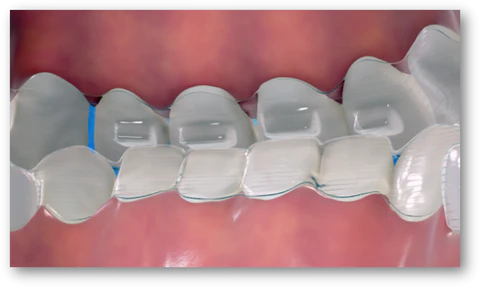

안녕하세요, 상봉동 교정치과 김정은 원장입니다. 치열이 가지런하지 않고 앞니가 겹쳐 보이는 전치부총생은 기능적인 문제뿐 아니라심미적인 부분과도 밀접하게 연결됩니다. 그렇기 때문에…